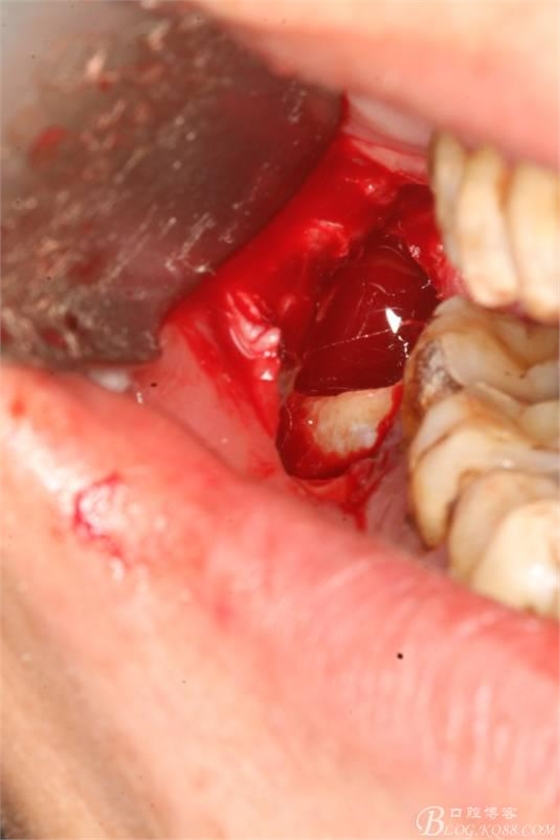

2.切開翻瓣

3.去骨、暴露48.

4.縱分牙根和牙冠